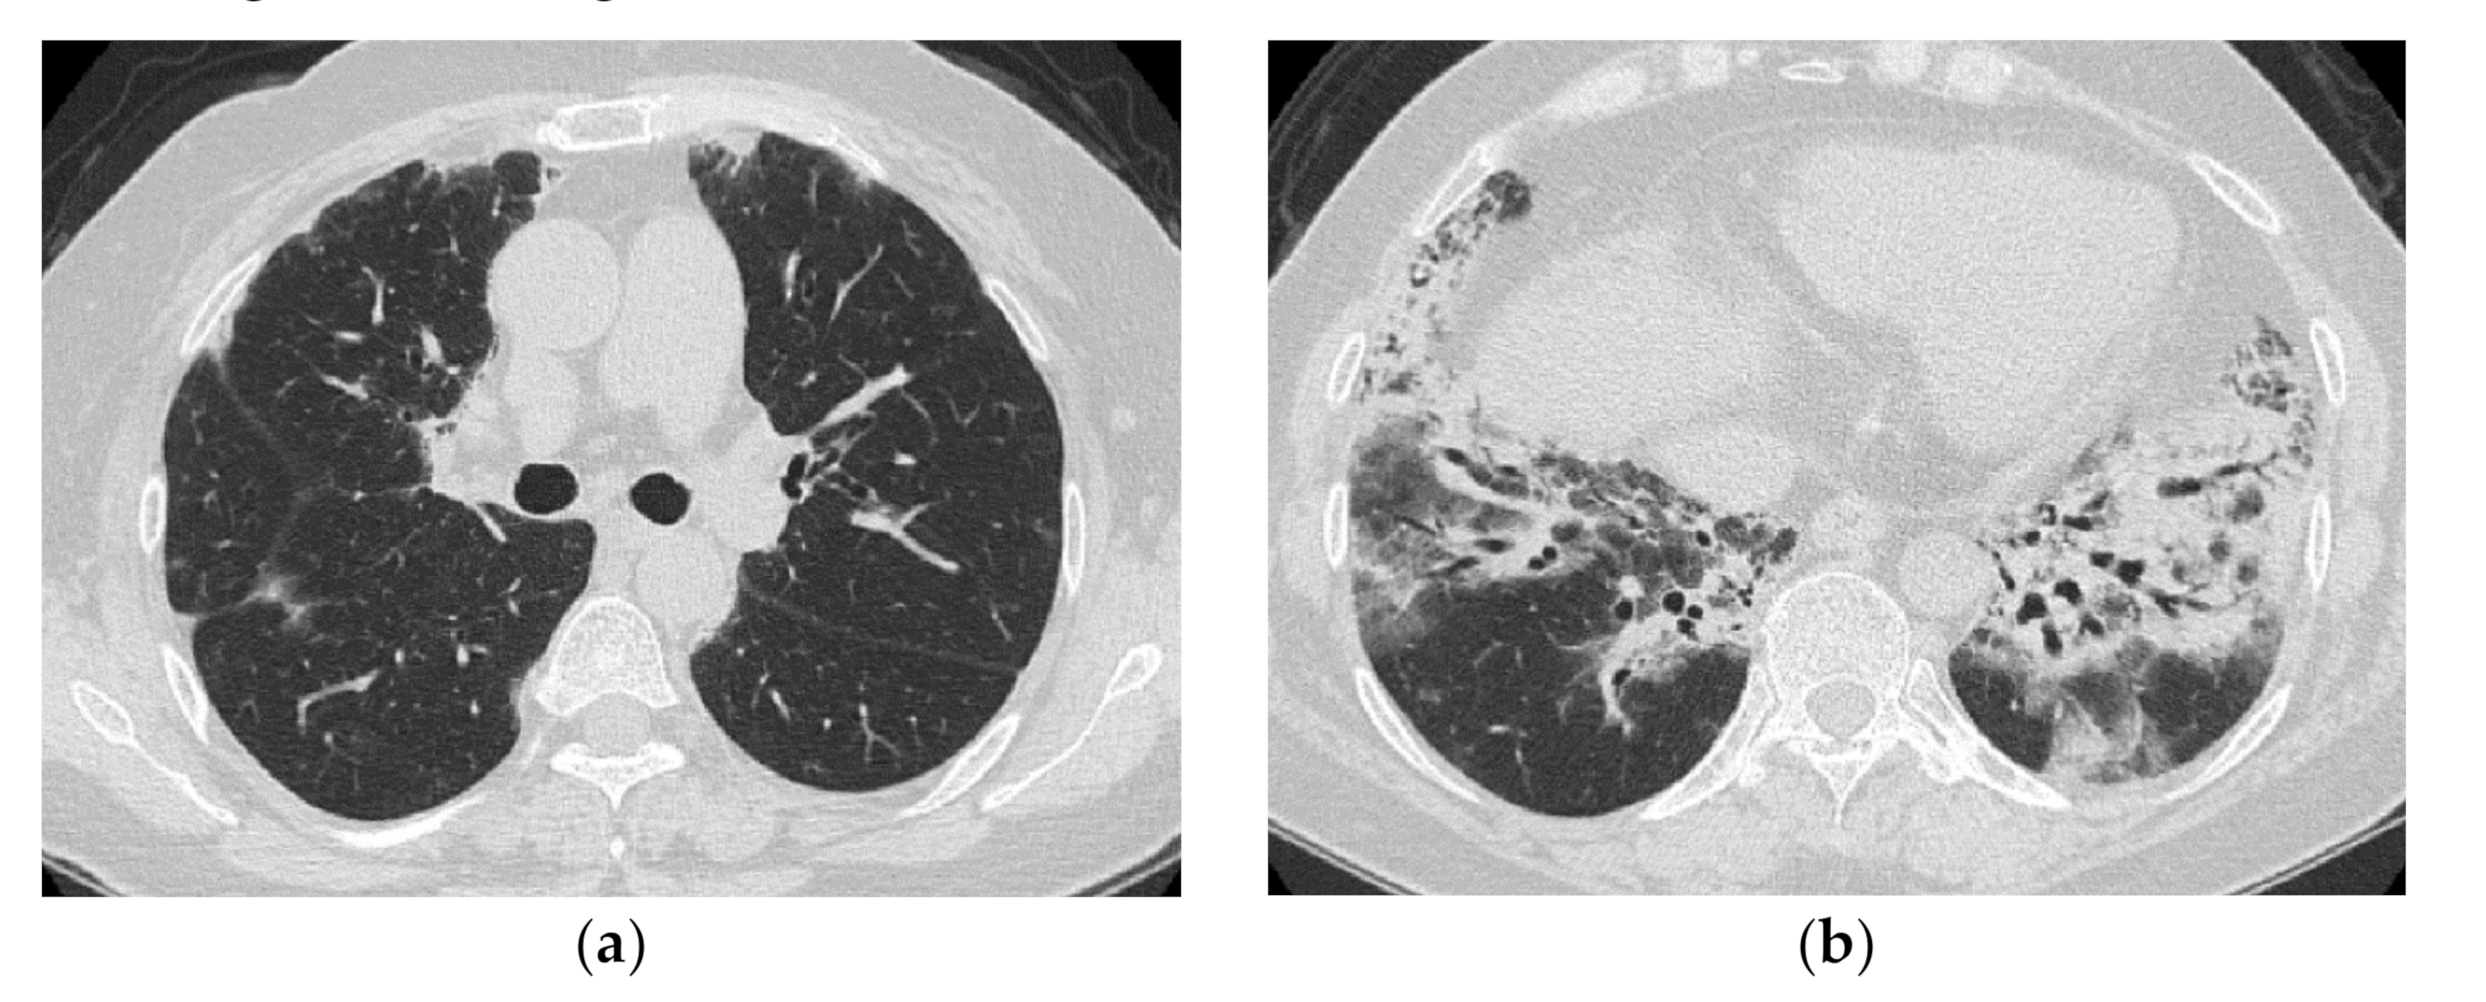

2.1. Subacute to Chronic Type

2.2. Acute Type